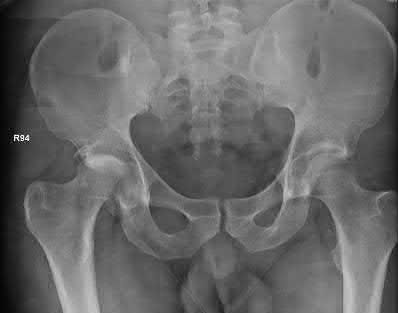

A 27 year-old patient sustains a fracture-dislocation of the acetabulum. Pelvic radiographs (Figures A and B) are taken at initial presentation and a CT scan (Figures C and D) is performed after reduction of the hip in the emergency room. What is the importance of the finding highlighted in the CT scan cuts?

The CT images shown in Figures C and D display significant marginal impaction of the joint surface.

Marginal impaction is common in posterior wall fractures and fracture-dislocations. Critical review of CT imaging of posterior wall fractures can help with preoperative planning for identifying impaction of the articular surface of the acetabulum. Restoration of the sphericity of the acetabulum to match that of the femoral head is important for successful outcome following ORIF of posterior wall fractures. A common surgical technique to accomplish joint surface restoration includes freeing the impacted articular segments, bone grafting of the void created to support the articular segments, and buttress plating of the posterior wall fracture fragments.

Figures A and B are radiographs of the posterior wall fracture and hip dislocation. They do not show the large amount of marginal impaction of the acetabular surface. Figure C (coronal reconstruction) and Figure D (sagittal reconstruction) point out a large a amount of marginal impaction of the acetabular. Note the disruption of the joint surface on the intact portion of the acetabulum.

A 44-year-old male presents after being struck by a car. He is hypotensive, and has an obvious open tibia and a closed femoral shaft fracture. A pelvic radiograph is obtained and shown in Figure A. A representative CT scan image in shown in Figure B. The patient is placed in a pelvic binder, and his blood pressure normalizes with crystalloid and a blood transfusion. He then undergoes pelvic angiography, and his internal iliac artery is embolized. Which of the following definitive treatment options is most appropriate in this case?

The radiographs and CT scan show a fracture pattern consistent with an APC-III injury. This is most appropriately treated with pubic symphysis ORIF with a multi-hole plate and posterior iliosacral screw fixation.

APC-III pelvic ring injuries are associated with with disruption of the anterior and posterior SI ligaments (SI dislocation) as well as disruption of

sacrospinous and sacrotuberous ligaments. They are commonly associated with vascular injury and retroperitoneal bleeding.